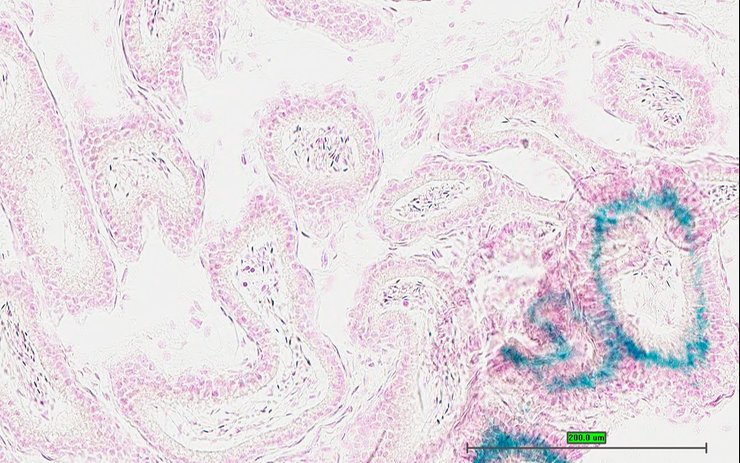

TS28: tongue Present UC Davis_1880325

TS28: tongue Present UC Davis_1880326

TS28: tongue Present UC Davis_1880320